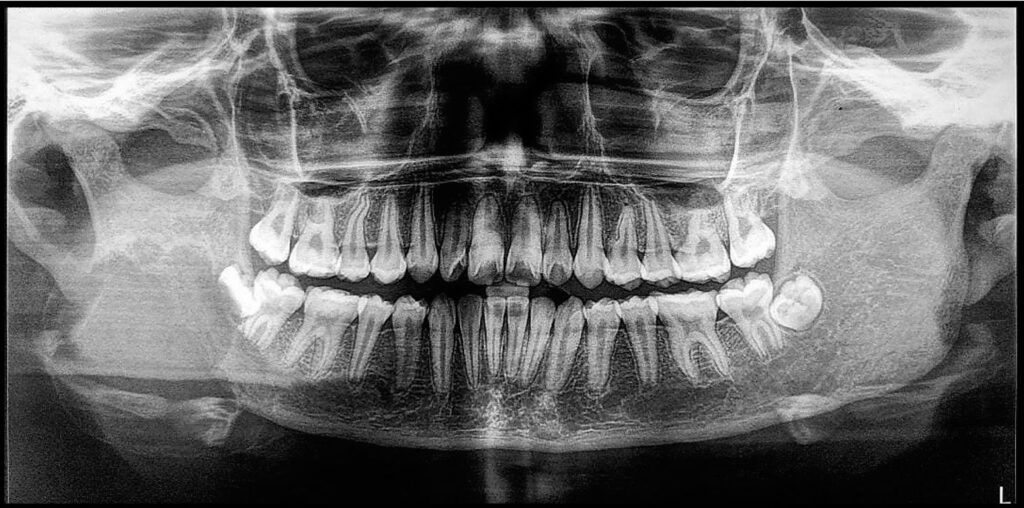

4-year-old boy with radiographic findings

A 4-year-old boy with unusual findings on a panoramic film.